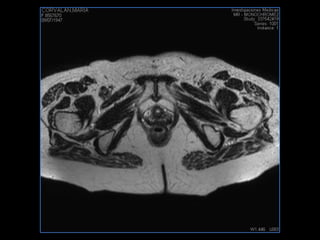

PROTOCOLO pelvis SAG T2, Y FAT SAT (FINOS) AXIAL T1  AX FAT SAT CON   GADOLINIO :  AX T1 Y COR T1 SAT: NO  FASE: RL THK: 3MM  COIL:  GAP: (FACTOR 1.4) 1MM FOV: 40 CM NEX:2 SINCRONIZACION RESPIRATORIA EN 3 O 4 CICLOS ALE

resonancia de abdomen